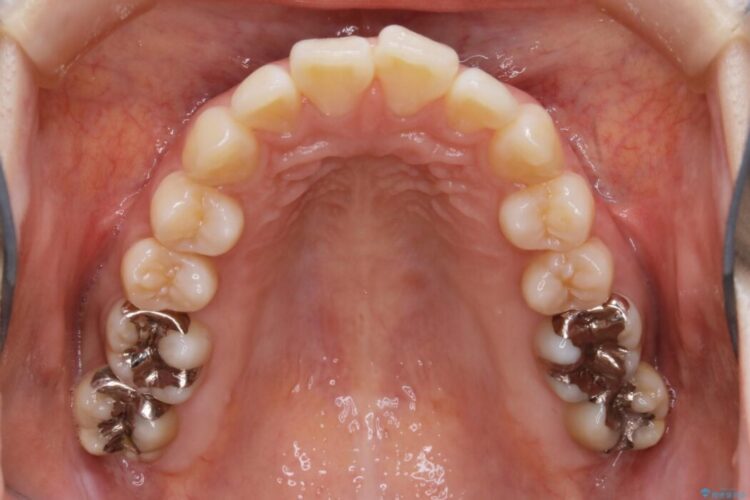

【20代女性】非抜歯でマウスピースの限界に挑戦する矯正治療

よって患者様ご希望の非抜歯かつマウスピースでの矯正を行うために、最大量の臼歯の遠心移動をして歯列全体を奥へ引っ込める計画をご提案しました。

治療後について

非抜歯での矯正治療

マウスピースにマイクロインプラントという補助装置を併用することで抜歯をせずとも歯列を整えるスペースを確保することができます。奥歯から順に移動させていくので前歯に変化が出るまでには時間がかかってしまいますが、健康な歯を抜歯することなく理想的な歯並びを手に入れることができます。